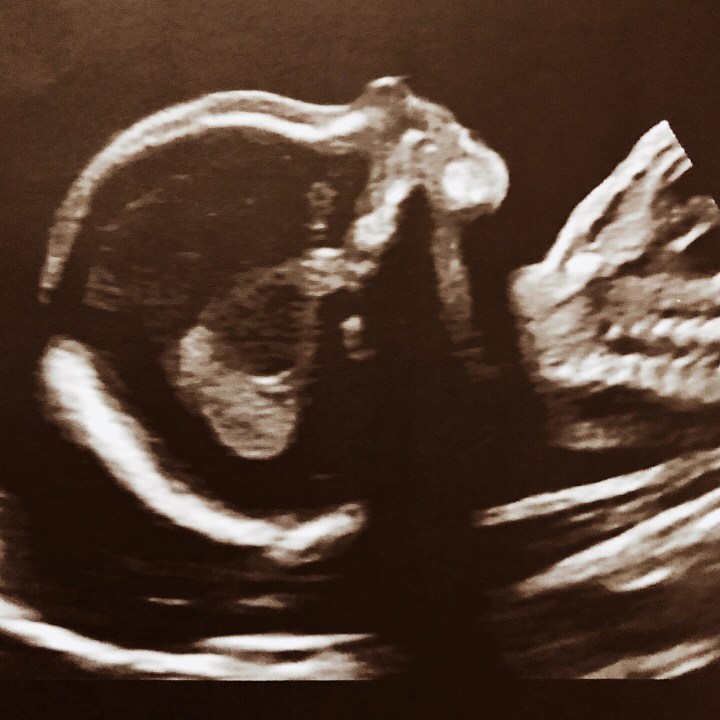

I went for another ultrasound scan on Monday to check on the development of our little person. It was quite a lengthy process as lots of images need to be captured to check that development is progressing as it should. Our baby was quite wriggly, making it a little tricky but after an hour or so we’d got all the stills that were required. Adam joined me and it was lovely to just stare up at the screen and watch our baby move about – we’re so excited to meet bub.